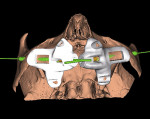

To overcome these drawbacks the present authors have designed a specific, novel surgical guide for the insertion of zygomatic implants that allows for visualization of the maxillary sinusal fenestration (Figure 3 and Figure 4). The surgical guides as presented were constructed using rapid prototyping, 3D printing (Objet Eden260V, Stratasys, stratasys.com), or a stereolithographic technique (Materalise, materialise.com) with biocompatible material (Med610, Stratasys) based on the 3D computerized implant planning from the CT/CBCT scan. Metal sleeves or guide cylinders used to guide the drills 4 mm in vertical height were manually inserted into the pre-defined holes in the resin during the finishing phase of the surgical guide.

The perimeter of the guide is specifically designed so that it extends on the lateral bone surface of the maxillary sinus and has an elongated section that follows and embraces the zygomatic process. This extended form (Figure 5) provides an prolonged area of support on the bone surface for improved stability and accompanies the drill until it reaches the zygomatic body, arriving very close to the exit point.

The support of the guide on both the zygomatic process and the lateral surface of the sinus wall is an essential component of the protocol, especially in comparison to the support provided by commonly fabricated surgical guides, which is limited by the alveolar bone crest. Importantly, in the interior of the guide a rectangular space oriented upward enables visualization of the sinus fenestration as well as lateral access to it, which, in accordance with the Chow technique,24 will be pushed inside of the maxillary sinus, protecting the Schneiderian membrane from the movement of the drills, and diminishing risks of sinusitis and oro-antral communication. Therefore, the retained bony window functions as a shield to protect the sinus membrane from direct damage by the drills. The sinus fenestration window follows the direction of the zygomatic implant and extends from the infra-zygomatic crest toward the back and upward, reaching the zygomatic body, and allows visual control of the drills during every phase of the preparation of the implant site on the zygomatic body. In case of two zygomatic implants as in the quad technique,37 the fenestration must be much wider to accommodate visualization of both implants (Figure 6).